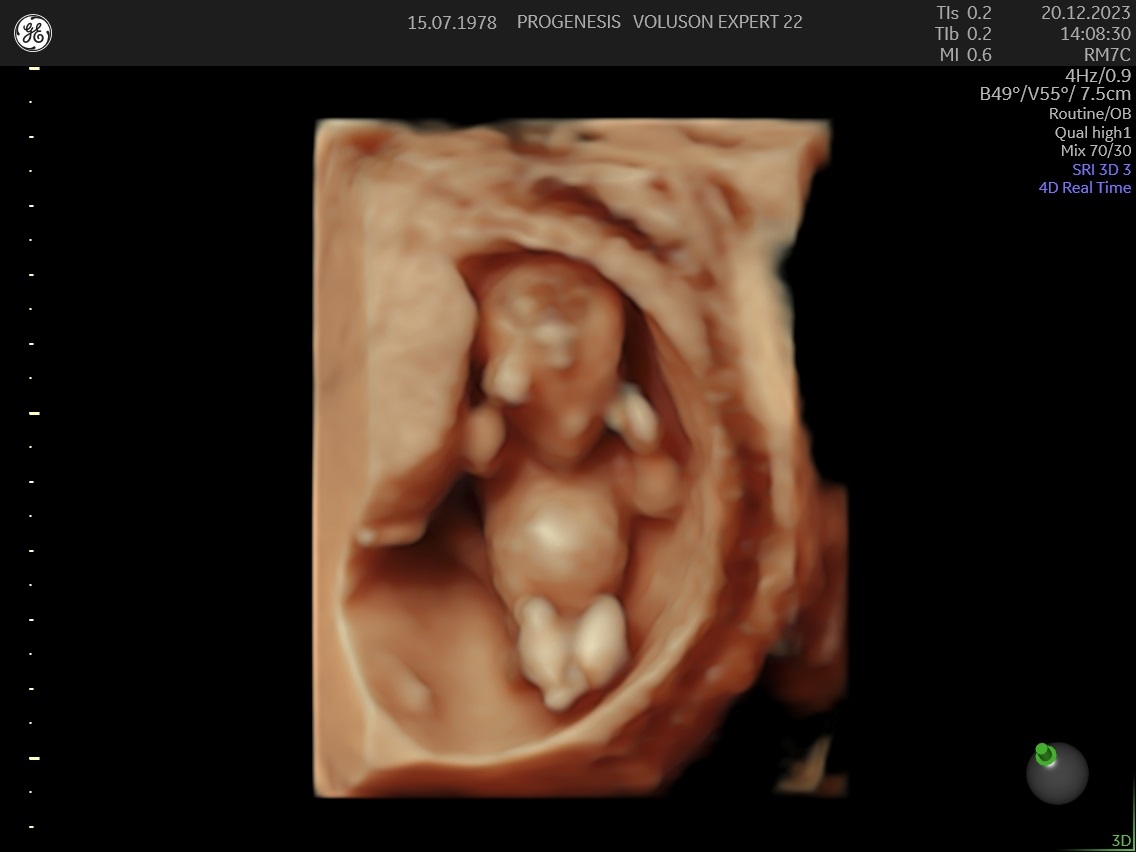

Υπερηχογράφημα Αυχενικής Διαφάνειας (11-14 εβδομάδων)

Το υπερηχογράφημα της αυχενικής διαφάνειας, πραγματοποιείται από τις 11 εβδομάδες +1 ημέρα έως 13 + 6 ημέρες κύησης και σε μήκος εμβρύου από 45mm έως 84mm.

Διάγνωση ανατομικών ανωμαλιών

Πολλές και σημαντικές ανωμαλίες, όπως ανεγκεφαλία, απουσία άκρων, ομφαλοκήλη, ορισμένες συγγενείς καρδιοπάθειες και άλλες ανωμαλίες, είναι ορατές απ' αυτό το στάδιο της κύησης. Δίνουμε ιδιαίτερη έμφαση στην αξιολόγηση της καρδιάς των εμβρύων, τόσο για την αξιολόγηση χρωμοσωμικών ανωμαλιών όσο και πρώιμη ανίχνευση συγγενών καρδιοπαθειών από το 1ο κιόλας τρίμηνο (π.χ. υποπλασία καρδιάς, συγγενή μετάθεση μεγάλων αγγείων).